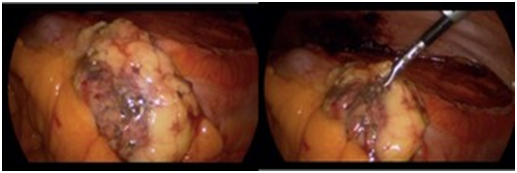

A 72 years old man was diagnosed with a small left renal mass incidentally during an ultrasonography for to an aortic abdominal aneurysm. A computer tomography (CT) scan confirm an exophytic 3cm left renal mass; therefore, an unclamped-laparoscopic partial nephrectomy was performed without difficulty. The tumor was placed inside of a plastic self-performed thermofused retrieval bag (Figure 1) and extracted trough a 12mm laparoscopic port. Finally, a drain was also placed close to the renorrhaphy. The patient was taken to the hospital room and in that moment, we realized that the bag was broken and the tumor was not inside. With the patient and family consent, a CT scan was performed showing a small mass next to the renorrhaphy (Figure 2); therefore, we decided to underwent an exploratory laparoscopy using the same port and patient position. Once laparoscopic camera was introduced, the tumor was found over the sigmoid colon slightly adhered (Figure 3) and extracted inside of a surgical glove. The hospital stay was 3 days with no perioperatory complications and the final histopathological finding was a 2cm cromophobo renal cell carcinoma with negative surgical margins.

Figure 3 Tumor over the sigmoid colon.